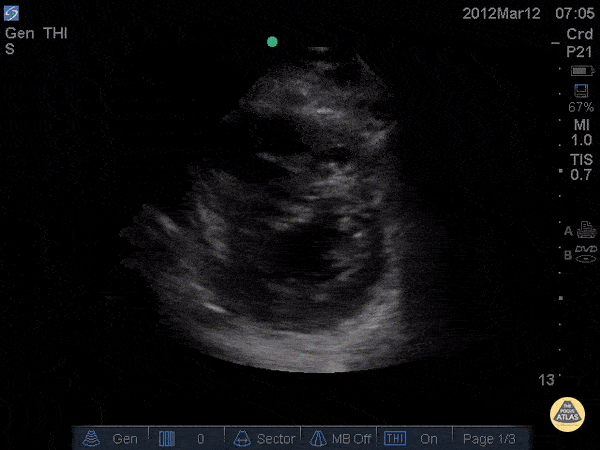

Right Ventricular Dysfunction - D-Sign in acute PE - Post TPA

34 y/o female no pmh with chest pain and rapid onset dyspnea on exertion noticed over 1 day. Patient became increasingly tachycardic and ultimately hypotensive so RUSH exam was performed showing D - Sign. CTA was subsequently performed and found to have saddle emboli. Echo was done pre and post TPA showing partial resolution of the D-sign. Dr. Joshua Schechter - Kings County Emergency Medicine